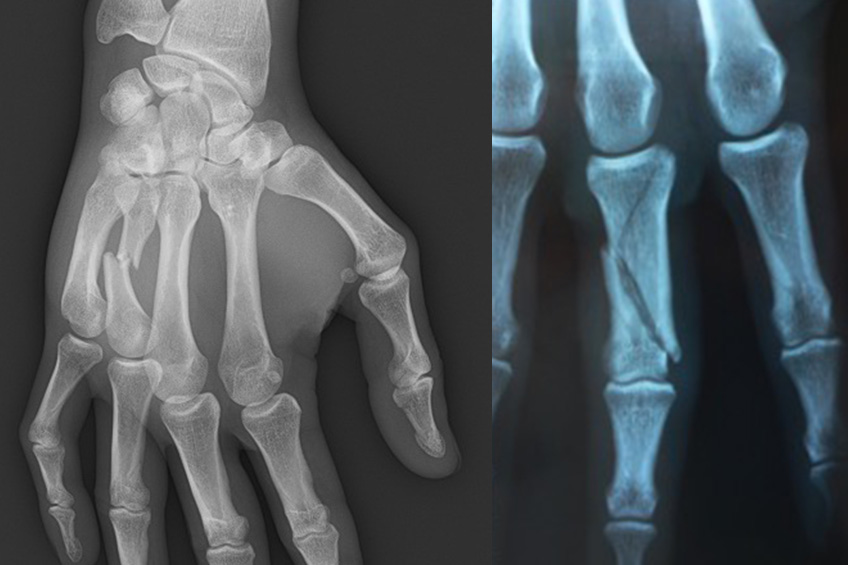

Le bilan initial doit comporter des radiographies permettant d’éliminer une fracture.

Les fractures de phalange et de métacarpien entraînent souvent des complications statiques et dynamiques de la main. Un avis spécialisé rapide est indispensable.